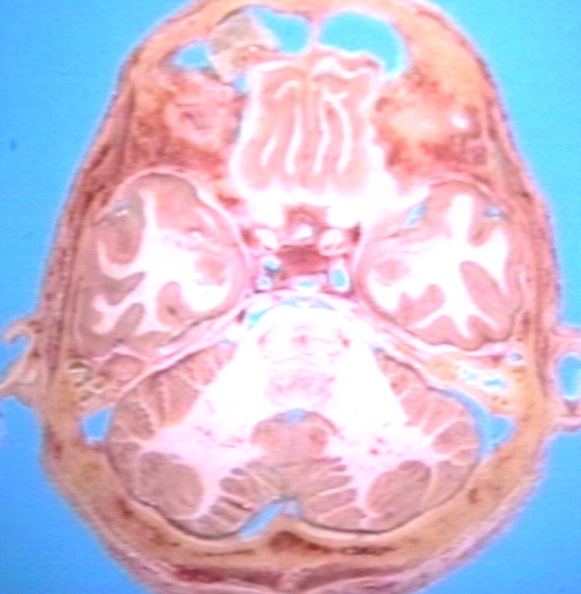

GROSS: NERVOUS: BRAIN: POSTERIOR FOSSA WITH CEREBELLUM AND PONS, TEMPORAL LOBE, ORBITAL CORTEX, CADAVERIC HORIZONTAL BRAIN SECTION

- PEIR Slice / Nervous / Gross